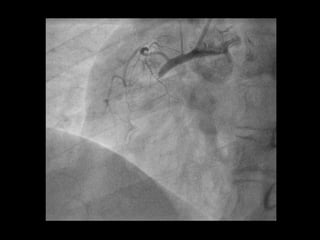

56 Jahre, weiblich

Seit 3 Tagen Herzschmerzen, zuletzt auch in Ruhe

Cholesterin

Familiäre Belastung

Übergewicht

Troponin T hs 67 pg/ml [0 -14]

EKG

Kardinal Schwarzenberg´sches Krankenhaus, Innere Medizin, Freitag 29. Juni 2012

NSTEMI - ACS 56Jahre, weiblich Seit 3 Tagen Herzschmerzen, zuletzt auch in Ruhe Cholesterin Familiäre Belastung Übergewicht Troponin T hs 67 pg/ml [0 -14] EKG Kardinal Schwarzenberg´sches Krankenhaus, Innere Medizin, Freitag 29. Juni 2012